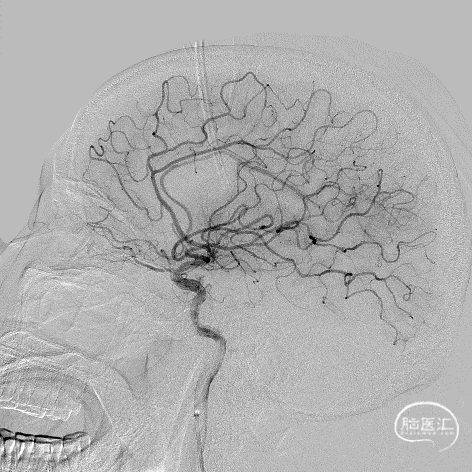

术前DSA影像:造影显示患者右侧大脑中动脉闭塞。

右侧颈内动脉造影—M1段闭塞